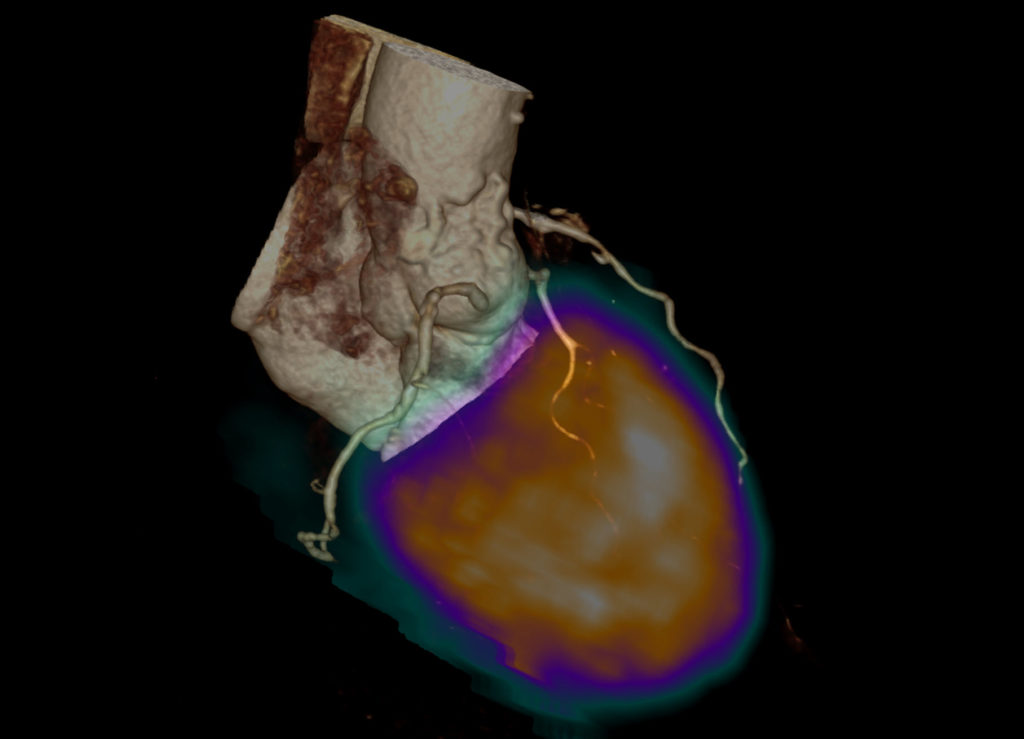

Bildbeispiele:

PET

3D-Rekonstruktion eines Herzens bestehend aus anatomischen Informationen, wie z.B. des Gefässverlaufes, sowie überlagert Informationen zur Durchblutung des linken Herzmuskels.